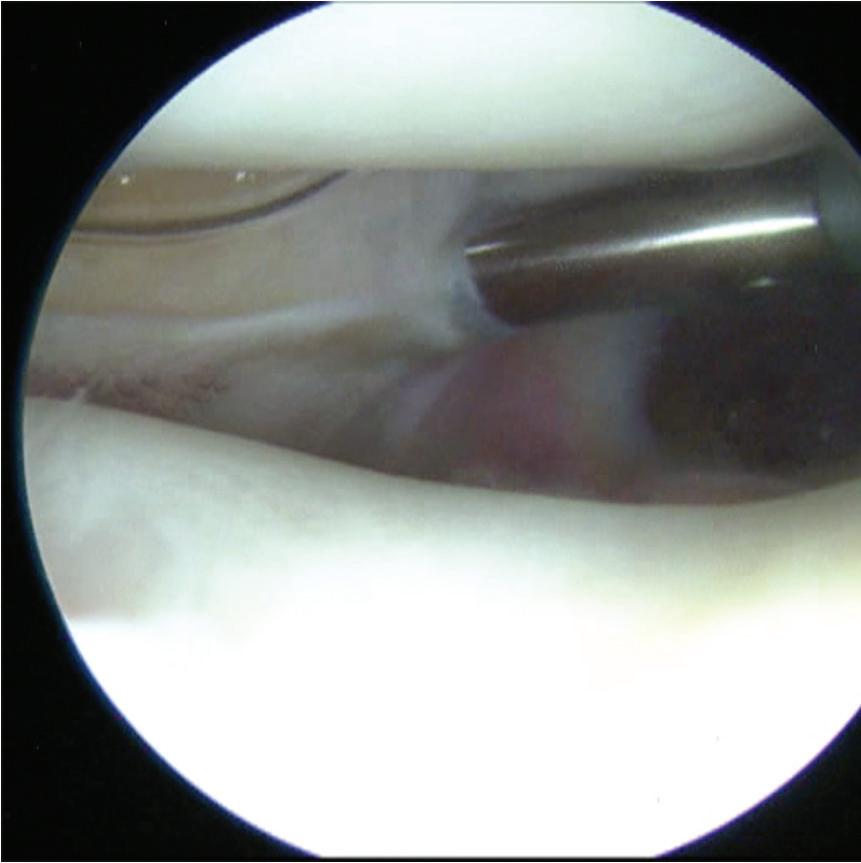

■ At this point, an 18-gauge spinal needle is placed into the portal site for the AM portal and is visualized arthroscopically (Fig. 1-6).

Figure 1-3 Arthroscopic photograph of the left knee shows the patellofemoral joint with the outflow cannula placed

Figure 1-4 Arthroscopic photograph of the left knee shows the patellofemoral joint in extension.